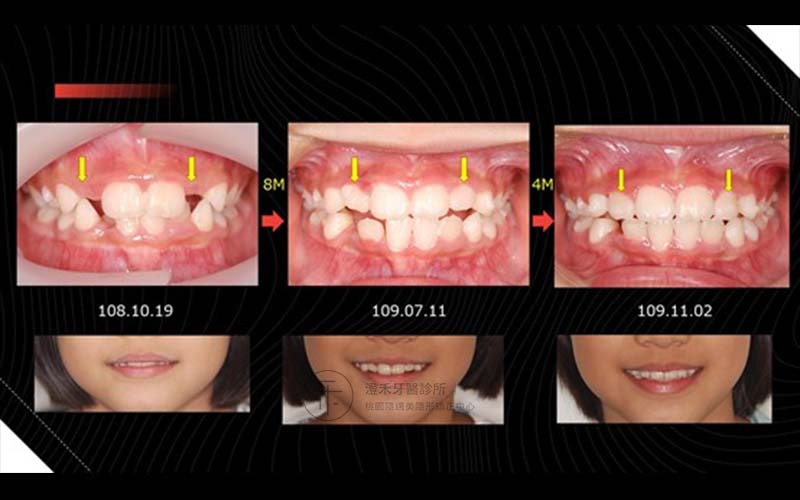

學齡兒童 目前:9歲

側門牙遲遲未長出,使用了兒童隱適美的矯正方式,牙齒已經有足夠的空間長出來。

矯正時間 : 1年